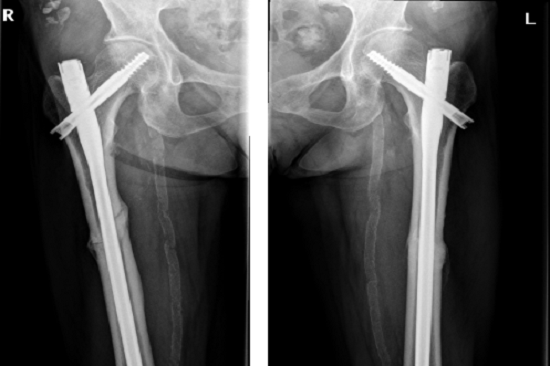

2018年上海交通大學醫學院附屬仁濟醫院創傷骨科碰到了一位從馬路臺階上摔倒的老年女性患者,拍片顯示是雙側股骨干近三分之一骨折(圖1),很對稱。

圖1

李占玉醫生團隊當時嚇了一跳,輕微暴力就能引起雙側股骨干骨折,這比較少見,肯定是病理性骨折,首先想到的是腫瘤所致,追問病史,患者否認有腫瘤病史,但有系統性紅斑狼瘡30多年,口服福善美5年,但已經停藥2年,在摔倒前有左側大腿根疼痛。根據病人的病史、體征和X線片所見,我們診斷為非典型股骨骨折,然后行髓內釘內固定術,術后8個月骨折愈合(圖2)。

圖2:髓內釘固定骨折,術后8個月,骨折愈合